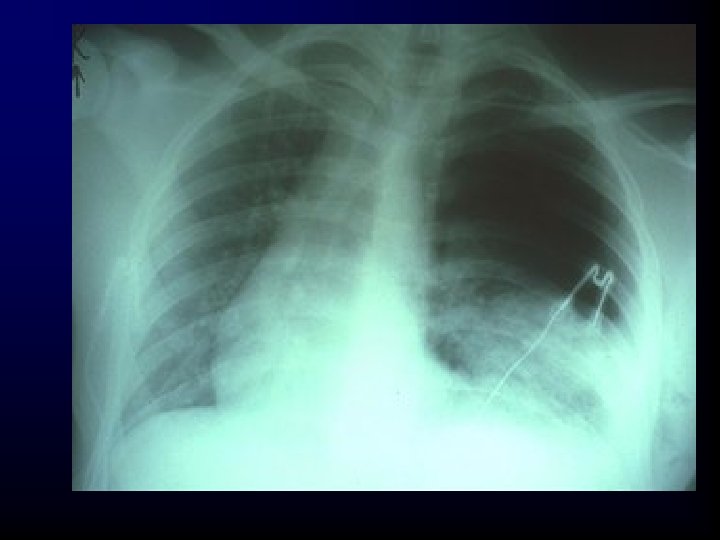

Hemothorax • If this condition is associated with pneumothorax, it is called a hemopneumothorax.

Hemothorax • Incidence – Associated with pneumothorax. – Blunt or penetrating trauma. – Rib fractures are frequent cause.

Hemothorax Morbidity/Mortality • A life-threatening injury that frequently requires urgent chest tube placement and/or surgery • Associated with great vessel or cardiac injury – 50% of these patients will die immediately. – 25% of these patients live 5 to 10 minutes. – 25% of these patients may live 30 minutes or longer.

Massive hemothorax • Rapid accumulation of >1500 cc blood in chest cavity • Hypovolemia & hypoxemia • Neck veins may be: – flat - from hypovolemia – distended - intrathoracic blood • Absent breath sounds, DULL to percussion

Hemothorax Assessment Findings • Tachypnea • Dyspnea • Cyanosis – Often not evident in hemorrhagic shock • Diminished or decreased breath sounds on the affected side

Hemothorax Assessment Findings • Hyporesonance (dullness on percussion) on the affected side • Hypotension • Narrowed pulse pressure • Tracheal deviation to the unaffected side (rare) • Pale, cool, moist skin